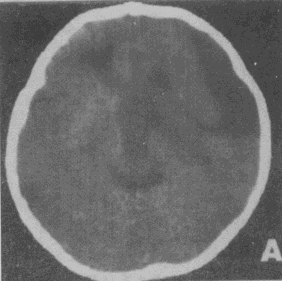

男性,12岁。智力低下、言语障CT检查如图所不,请根据CT图像诊断 YZ332_1_45_15.gif YZ332_1_45_15.gif

• A.蛛网膜囊肿

• B.脑裂畸形

• C.Dandy-Wallker综合征

• D.囊性胶质瘤

• E.左侧侧脑室室间孔闭锁或狭窄